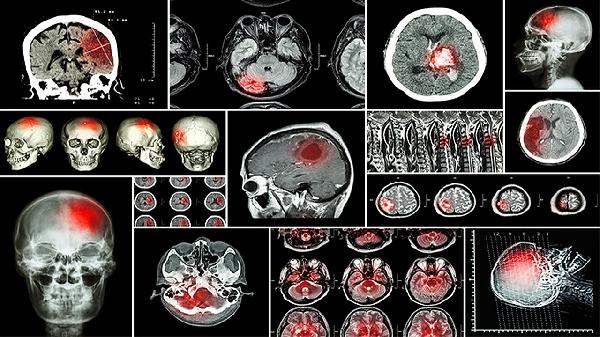

舒脑欣滴丸具有改善脑部血液循环、缓解血管性头痛、调节脑血管功能等作用,主要用于脑供血不足引起的头晕头痛等症状。舒脑欣滴丸的主要成分包含川芎、当归等中药材,其作用机理主要有扩张脑血管、抑制血小板聚集、抗氧化、减轻脑组织损伤、促进神经功能恢复。

舒脑欣滴丸中的川芎嗪等成分可选择性扩张脑血管,增加脑血流灌注,改善脑组织缺血缺氧状态。适用于因脑血管痉挛或动脉硬化导致的脑供血不足,表现为反复发作的头痛头晕。用药期间需监测血压变化,避免脑血管过度扩张引发不适。

方中多种酚类化合物可清除氧自由基,减轻缺血再灌注对脑细胞的氧化损伤。对于动脉粥样硬化引起的慢性脑缺血,能保护血管内皮功能,延缓脑血管病变进展。长期使用需定期复查肝功能。

4、减轻脑组织损伤

药物通过上调脑内神经营养因子表达,减少缺氧状态下神经细胞凋亡,对急性脑缺血后遗症具有神经保护作用。临床多用于脑卒中恢复期伴随的认知功能障碍,需配合康复训练使用。